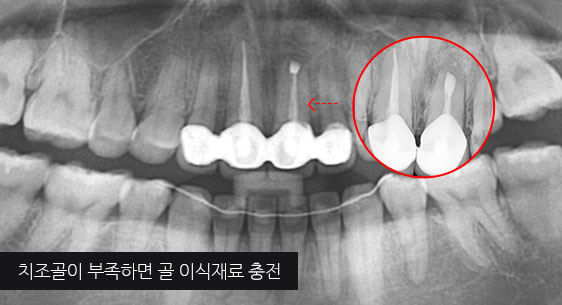

심한 염증으로 치조골이 광범위하게 소실, 아래쪽 신경관이 가까이 있어 치근단수술이 불가능한 상태, 타 병원에서 임플란트 진단을 받았지만, 고운미소치과에서 치아를 발치하고 뿌리 쪽 염증을 제거한 후 발치한 치아를 다시 심는 치아재식술을 시행하였습니다.

기존 신경치료 부위에 염증과 치조골이 소실되고 있는 상태

치아를 발치하고 염증을 제거, MTA로 충전하고

치아를 다시 심음. (난이도 중)